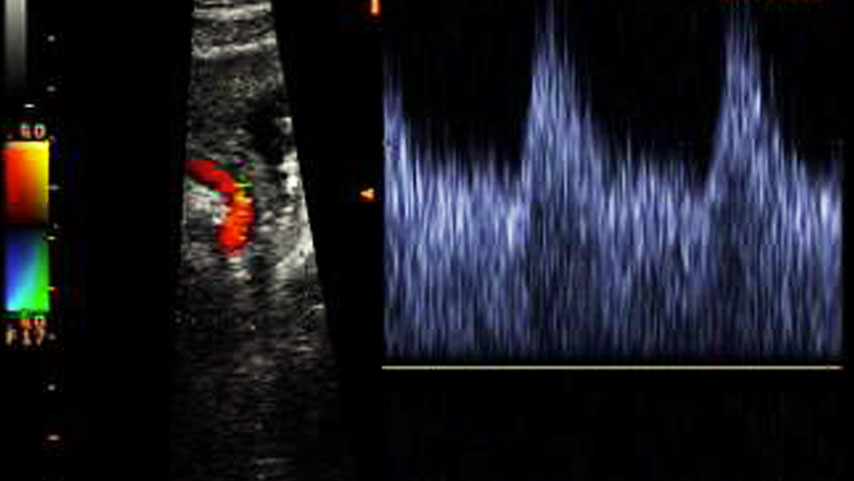

Doppler flussimetria delle arterie uterine

Sulla sinistra, in rosso l'arteria uterina di cui si rileva il segnale. Sulla destra, l'onda di flusso registrada dal Doppler